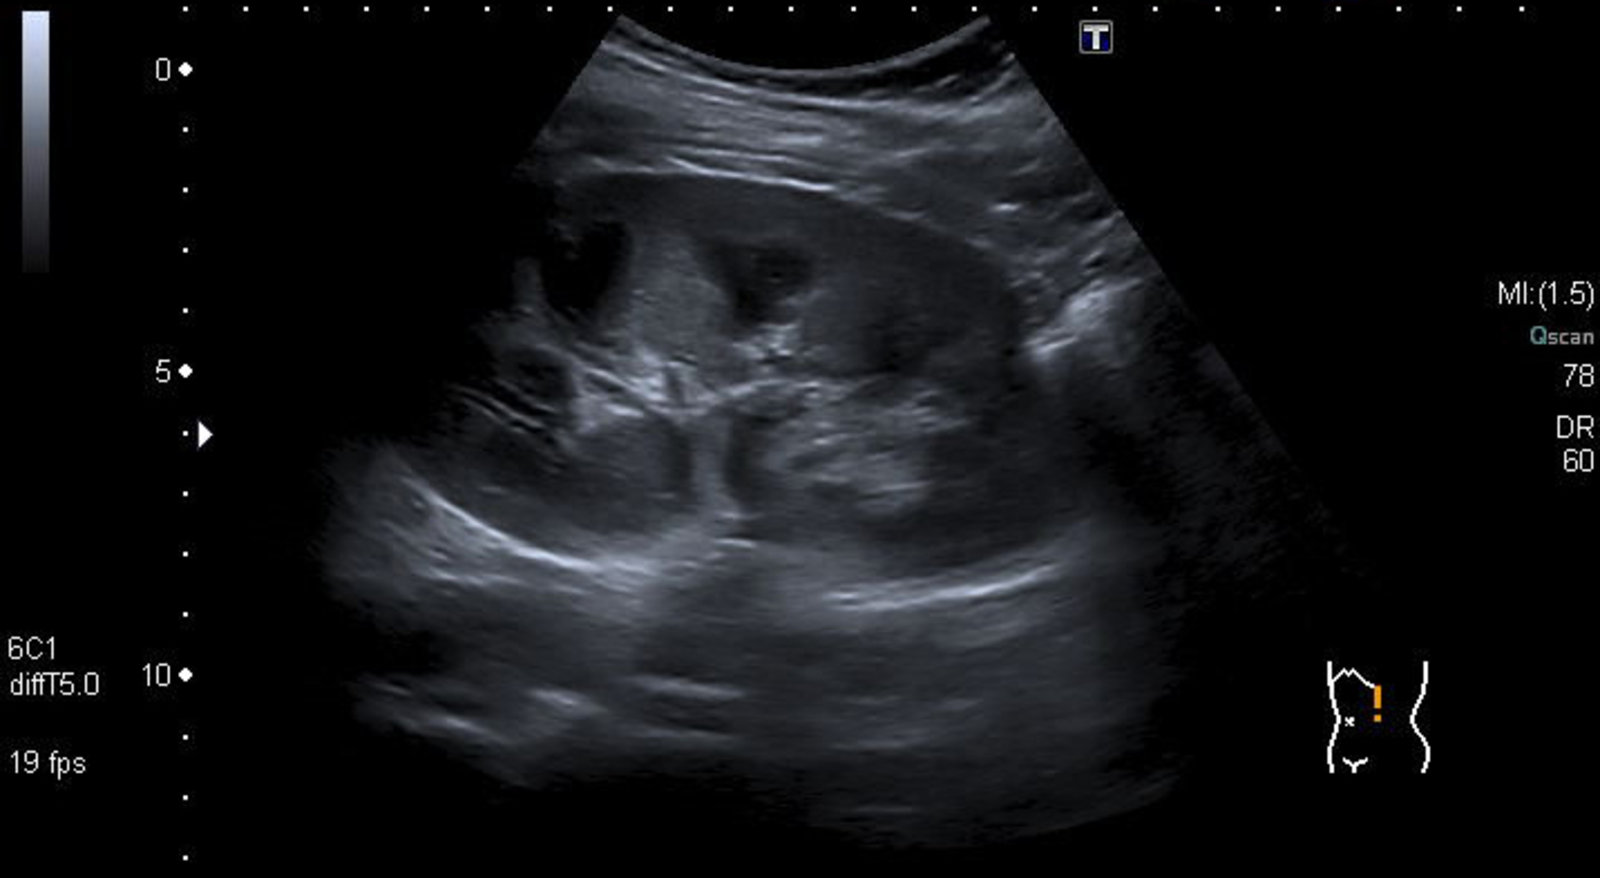

Renal ultrasound [5]

• Indication: to rule out other causes of AKI

• Findings

• Often normal

• May demonstrate enlarged kidneys with increased echogenicity, reflecting interstitial edema [3]

• Renal ultrasound [9]

• Obtain to rule out other causes of CKD (not used to confirm or exclude the diagnosis of CTIN).

• Typically, small kidneys with increased echogenicity

• Normal to large echogenic kidneys may be seen in infiltrative tubulointerstitial diseases (e.g., sarcoidosis, lymphoma).

• Renal ultrasound [21]

• Quick, noninvasive initial test to assess for hydronephrosis, tumors, or calculi

• Findings: increased echogenicity of the inner medulla; filling defect in the medullary tip (late finding)